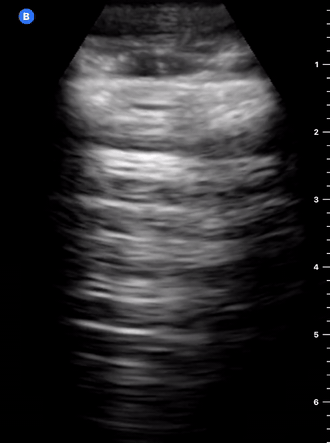

B-PROFILE: LUNG ROCKETS

The presence of pathological B-lines describes a B-profile. Widespread, bilateral, and/or three or more per window are considered pathological.

Multiple B-lines in a single window are described as lung rockets because they resemble a rocket at liftoff. The magnitude of the rockets correlates with the severity of the interstitial syndrome.

IS comprises pulmonary oedema, widespread pneumonia, acute respiratory distress syndrome, alveolar haemorrhage, and chronic interstitial diseases (for example, widespread fibrosis). The diagnostic approach will depend on the clinical context and the specific features of the image. Accordingly, a breathless patient developing acute pulmonary oedema will likely show diffuse, bilateral lung rockets, whereas a patient with ARDS will have patchy, asymmetrical B-lines.

Focalized pathological lung rockets, however, represent a differential diagnosis and can be found in various other disease processes such as focal pneumonia, pulmonary contusion, pulmonary infarction, cancer, or pleural disease.

Alternatively, the presence or evolution of B-lines can be used to guide fluid resuscitation and diuresis. For example, the development of lung rockets during aggressive intravenous fluid administration should represent a warning sign to stop or slow down fluids.